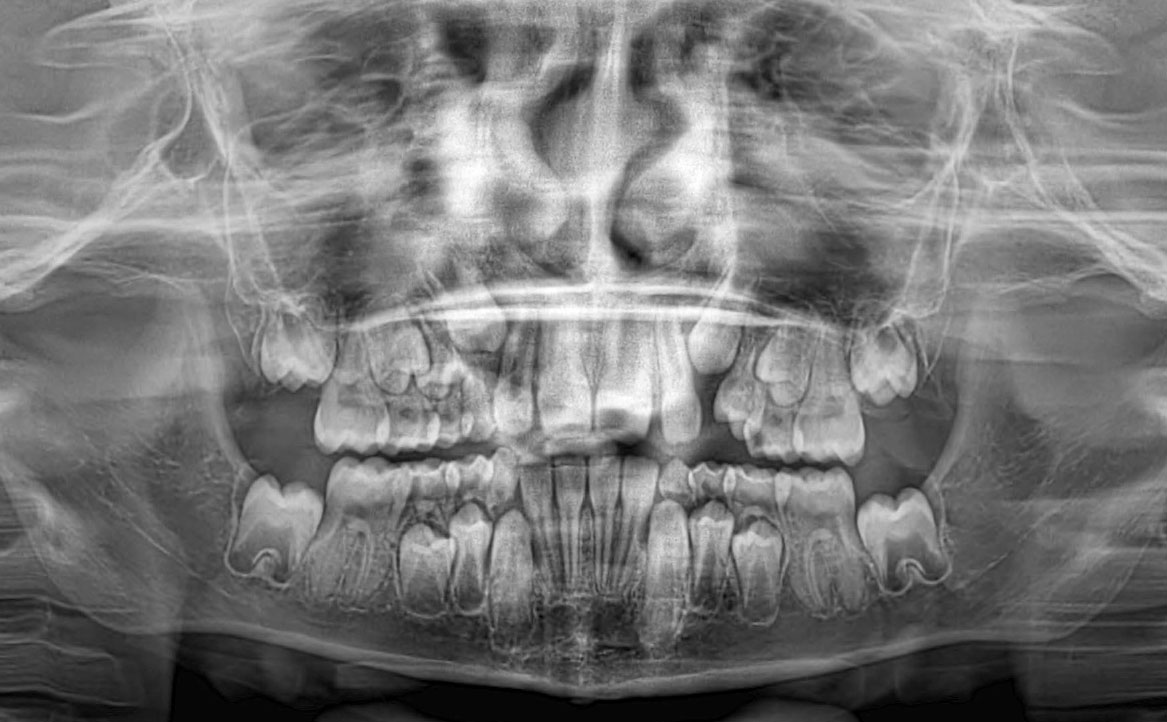

L’ortopantomografia mostra una fase di dentizione mista con presenza di tutti gli elementi dentari permanenti ad eccezione dei terzi molari.

Dal tracciato cefalometrico eseguito su teleradiografia L/L ne risulta I classe scheletrica (tendente alla III classe) ipodivergente con retroinclinazione degli incisivi superiori e proinclinazione degli incisivi inferiori (fig. 2-3).

Fig. 2 OPT.